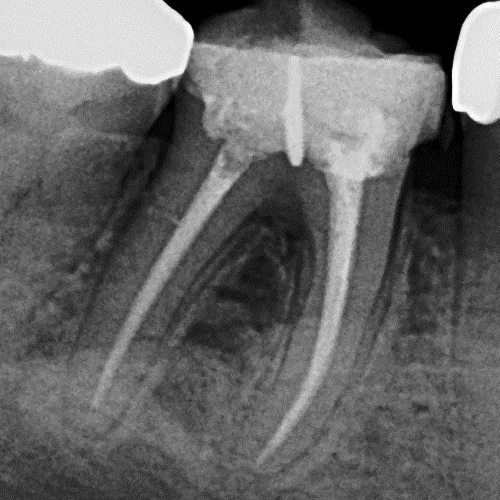

The treatment includes making a small opening in the tooth to remove the nerve and infection, cleaning inside the roots to the tip. An antibacterial dressing is placed inside the tooth and sealed with a temporary filling. Once the root canals are cleaned, the roots can then be filled and sealed to prevent bacterial recontamination. This procedure usually takes three sessions at least one week apart, but teeth with multiple root canals or significant infection may need more visits.

Once the root canal treatment is complete, it is important to protect the remaining tooth structure from breakage. This may be with a filling or a crown, depending on how much of the tooth is remaining.